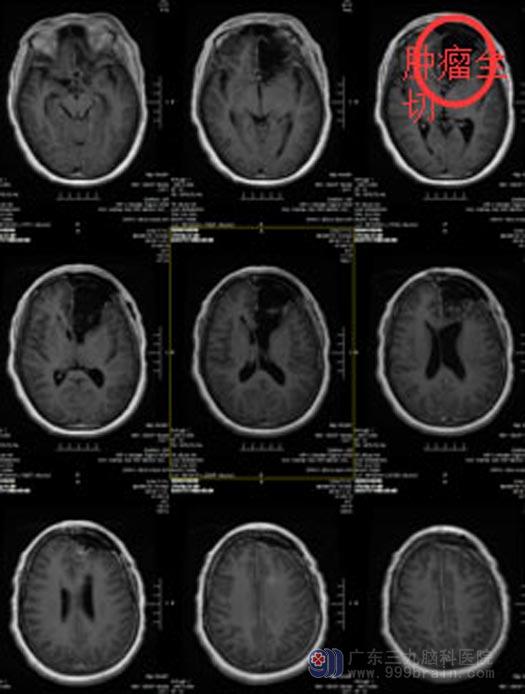

和患者及家属充分沟通后,由鲁明主任主刀行唤醒麻醉下左侧额叶—胼胝体占位病变切除术。利用导航准确定位肿瘤的位置,手术中唤醒郑女士,与她交流,缓解她紧张情绪,电生理检测运动中枢的同时让她完成指定动作。显微镜下将肿瘤完整切除,手术后郑女士肢体运动、感觉、语言等功能都表现正常。

手术后